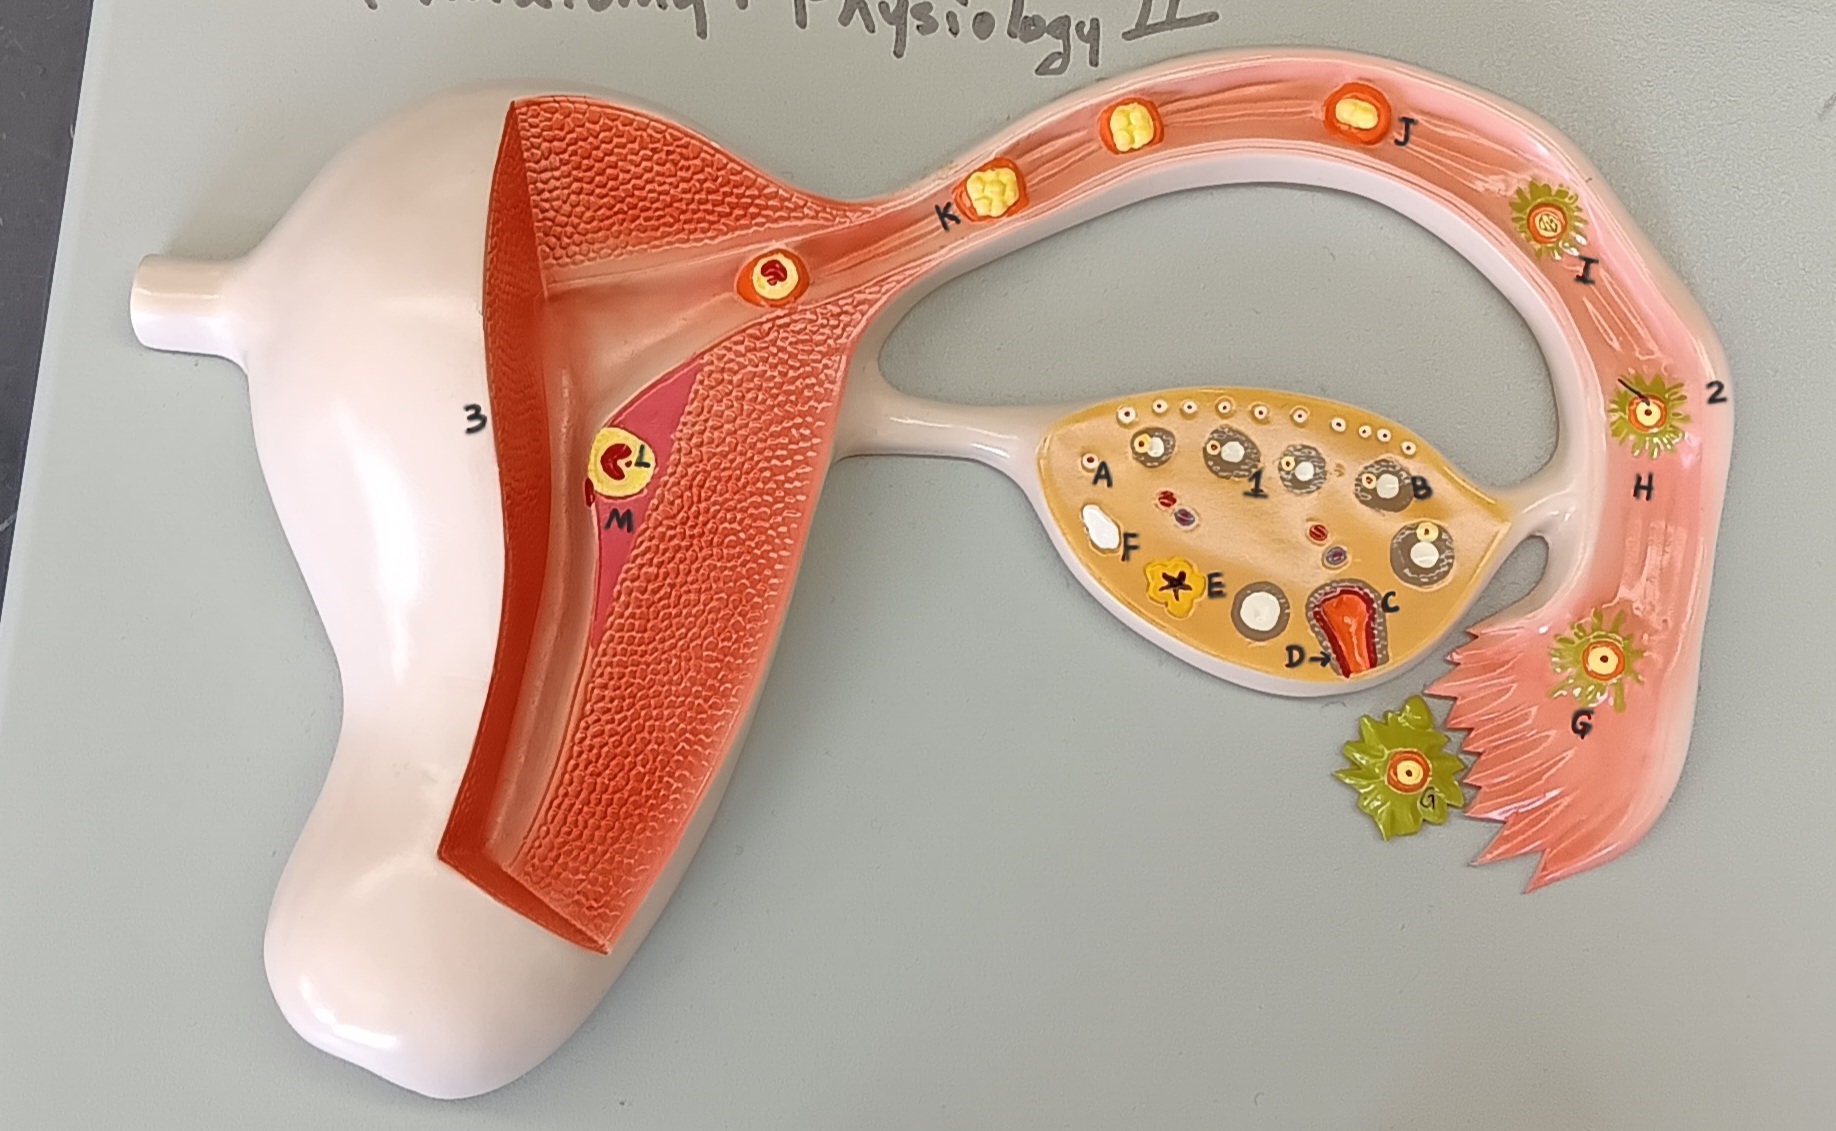

ovary

1

primordial follicle

a

secondary follicle

b

ruptured follicle

c

granulosa cells

d

corpus luteum

e

secondary oocyte

g

ovum

h

zygote

i

blastocyst

l

endometrium

m

corpus albicans

f

uterus

3

fallopian tube

2